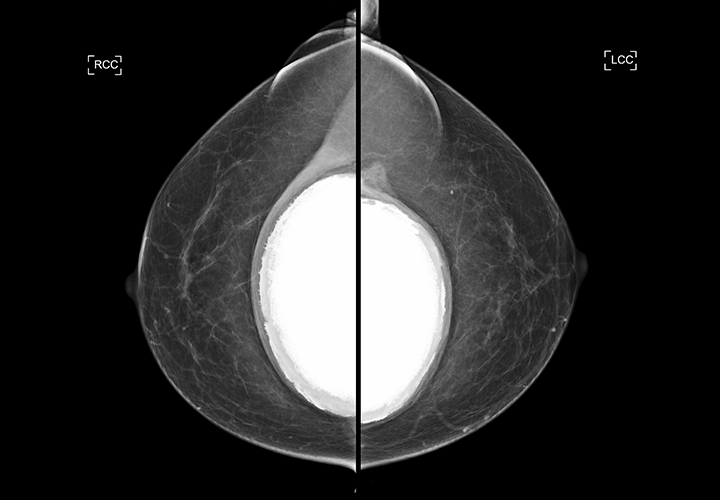

보형물 파열은 보형물의 외피(쉘)에 손상이 발생해

내부 내용물이 변형되거나 일부가 주변으로

이동하는 현상입니다.

통증이 없더라도 초음파 검사에서 파열이

확인되는 경우가 있습니다.

겉모습만으로는 파열 여부를 판단하기 어렵습니다.

보형물 파열은 통증보다 형태 변화에서 먼저 나타나는 경우가 많습니다.

파열 진단의 핵심은 구조를 정확히 이해하는 것입니다.